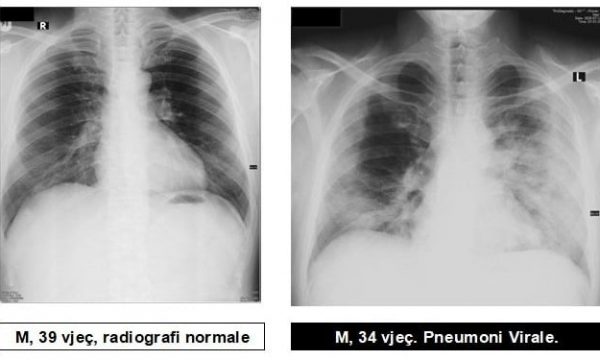

Radiologu në Spitalin Rajonal të Prizrenit, Sylejman Krasniqi tregon pamjet e mushkërive të pacientëve me pneumoni virale.

Imazhet e mushkërive me pneumoni virale